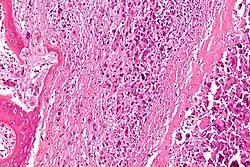

El cirujano puede realizar una biopsia de aguja o una biopsia por incisión. En una biopsia de aguja, el cirujano hace un hoyo pequeño en el hueso y extrae una muestra de tejido del tumor con un instrumento como una aguja. En una biopsia por incisión, el cirujano hace un corte en el tumor y extrae una muestra de tejido. Las biopsias las hacen mejor los oncólogos ortopedas, médicos con experiencia en el diagnóstico de cáncer de hueso. Un patólogo, médico que identifica las enfermedades al estudiar las células y tejidos en el microscopio, examina el tejido para determinar si es canceroso.